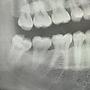

[問題] 這種智齒好拔嗎?

13Ffp737: 這種算小兒科吧04/25 21:07